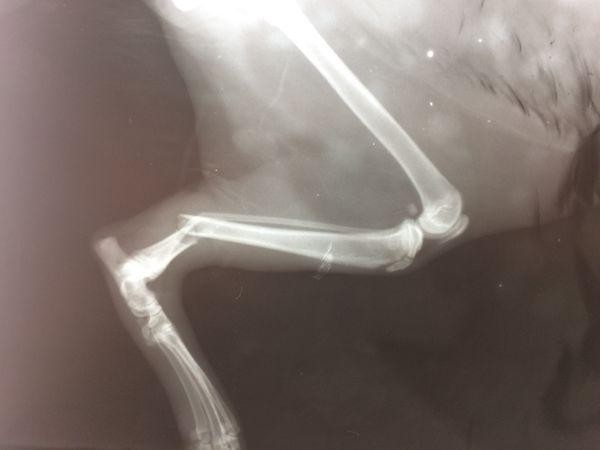

Травма – это повреждение органов или тканей животных. Они случаются из-за падений, ударов, ранений или ожогов. Есть разные виды травм: ушибы, растяжения, переломы, раны, укусы и ожоги.Мы можем заметить травму по тому, как животное ходит. Или просто осмотреть его. Например, если у животного перелом – оно будет хромать или лежать неподвижно.Если у животного рана – ее можно увидеть на поверхности кожи.

Когда кошка получает травму, она может стать агрессивной или спрятаться от вас.Осторожно осмотрите кошку. Если кошка лежит неподвижно – у нее может быть травма головы или позвоночника. В таком случае нельзя поднимать кошку. Если животное хромает – отвезите ее к ветеринару.